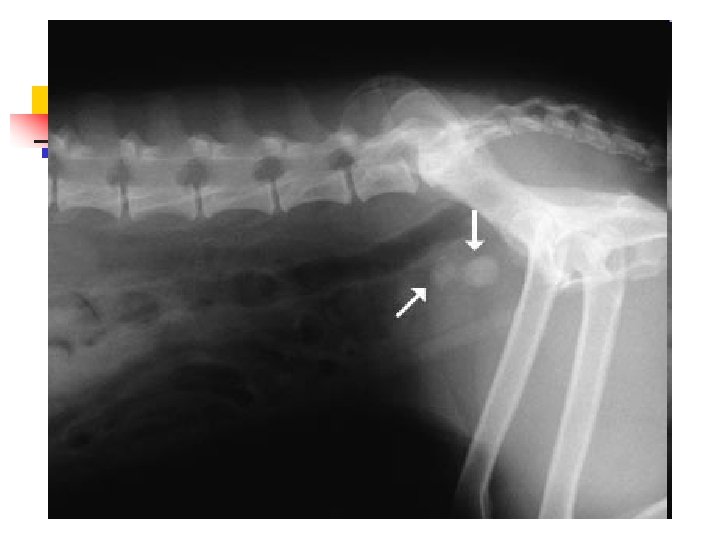

Bladder Stones n n Because most stones contain calcium, they are usually visible on a radiograph as white (bone density) objects in the area of the bladder. Sometimes there is a single large stone, and sometimes there are literally hundreds of tiny stones like sand or aquarium gravel.

When Lameness isn’t Simple n n Sometimes when an animal limps the cause turns out to be something more serious than a simple injury. The doctors palpated a firm, painful lump in the leg this dog was favoring. Radiographs showed that the bone was expanded in that area, with a motheaten, hollowed-out center. These are classic signs of a tumor in the bone, known as an osteosarcoma.